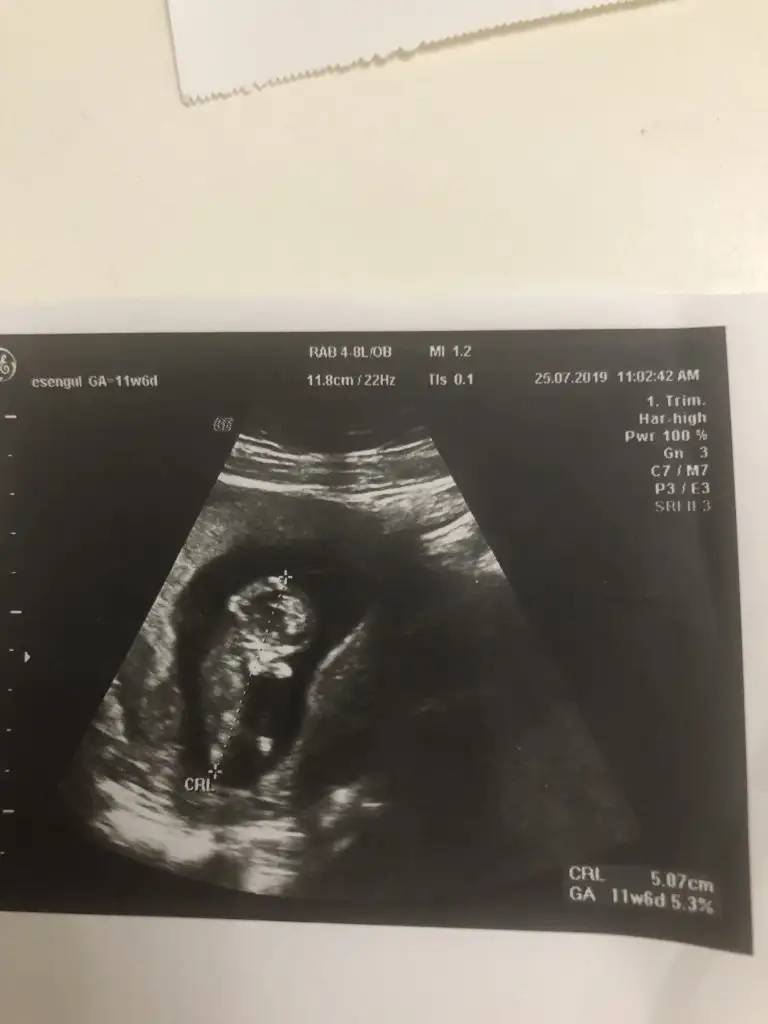

Erkek gibi11 haftalıktahmin alabilirmiyim

Erkek gibi kafa sekline yorumluyorum nub artık olmaz 13 hafta sanırımArkadaşlar daha önce yorum yapmıştınız ama doktor kesin bişey söylemiyor bunada bakabilir misiniz

Tam dik degil ama ben tahminimi Erkek gibi yorumluyorum